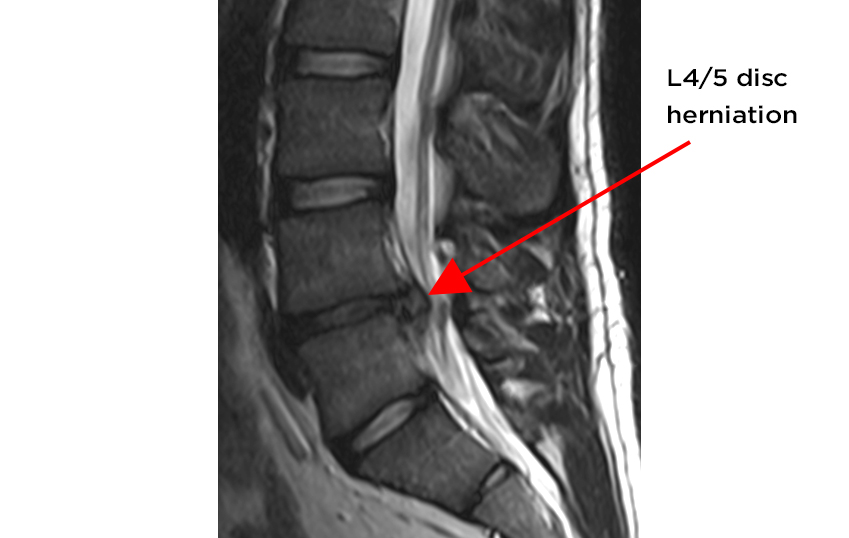

A condition known as a disc bulge (also referred to as a 'slipped' disc) is when the soft, jelly-like contents inside the disc bulges or pushes towards its outer edges, sometimes causing back pain. This bulge can also press on a nerve causing nerve pain. The terms bulge and herniation are sometimes used interchangeably, however a herniation should be considered a more severe injury as the disc contents with a herniation push through the disc's the outer edges.

While physiotherapy tests are helpful, scans (MRI or CT) can identify with good accuracy if a disc bulge exists. It is however very important to realise not all disc bulges or herniations are symptomatic! This raises the question of whether a scan is necessary- a discussion which you should have with an experienced physiotherapist. Note the following study by Boden and colleagues in 1990 to demonstrate my point. In a group of 67 people who had never had low back pain or sciatica, about one-third had substantial abnormality on MRI scans, including disc bulges and herniations. This shows us that just because a disc bulge or herniation is present, it does not always mean that there will be associated pain.